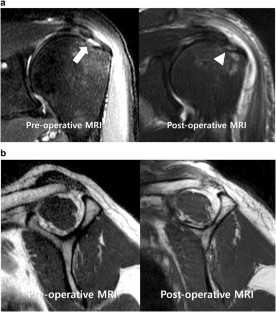

Fig. 1